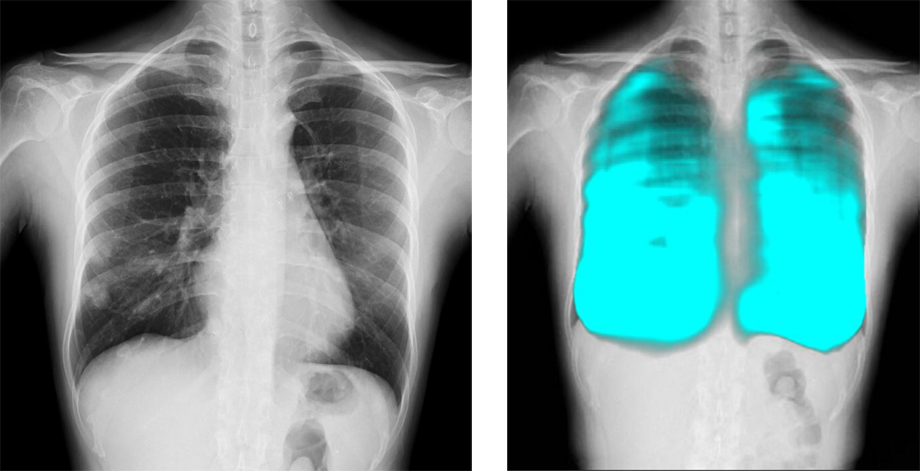

コニカミノルタのX線動態解析技術/イメージングAI技術と、FPTの高度なAI技術を活用し、呼吸器疾患の診断支援、医療レポートの自動生成など新しい診断技術の確立を目指す。コニカミノルタ独自の「X線動態解析」は、世界で300件以上の特許を取得しており、既に400台以上の販売実績がある。ベトナムの医療イノベーションとデジタル変革による呼吸器疾患対策を推進することで、国民の健康と医療従事者の負担軽減に貢献する。

■簡易かつ高度なX線動態解析画像を用いた呼吸器疾患に関する医療指標の開発と、AI診断支援ツールの開発による呼吸器疾患の早期診断機会創出

コニカミノルタはデジタルX線動態撮影および動態解析を、新しい“動きの診断”を提供するソリューションとして展開している。この同社独自の技術「X線動態解析」を搭載したシステムとして、一般X線撮影装置を用いて動画を撮影できるデジタルX線動態撮影システムを開発・提供しており、既に国内外の医療機関で導入実績がある。